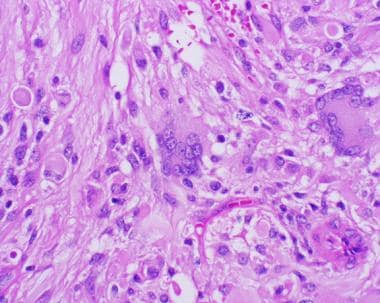

多形性黃色星形細(xì)胞瘤的特征是細(xì)長(zhǎng)的梭形細(xì)胞,胞質(zhì)嗜酸性,偶爾有巨細(xì)胞,其中一些可能表現(xiàn)為泡沫狀或黃色改變(見下圖)。嗜酸性顆粒體,一種病因未知的退化性細(xì)胞現(xiàn)象,也可能在毛細(xì)胞星形細(xì)胞瘤中遇到,幾乎總是存在。 這些腫瘤中的大多數(shù)還表現(xiàn)出細(xì)胞周網(wǎng)狀蛋白,這一特征較初被認(rèn)為是診斷性的,但后來發(fā)現(xiàn)不太可靠。網(wǎng)狀蛋白對(duì)應(yīng)于與每個(gè)腫瘤細(xì)胞相關(guān)的基底膜。淋巴細(xì)胞和漿細(xì)胞浸潤(rùn)也是常見的發(fā)現(xiàn)。

多形性黃色星形細(xì)胞瘤

多形性黃色星形細(xì)胞瘤的特征是大的多核細(xì)胞,胞質(zhì)呈泡沫狀,通常混有一群較小的纖維細(xì)胞。腫瘤細(xì)胞的細(xì)胞邊界通常獨(dú)特。(蘇木精和曙紅,20倍原始放大倍數(shù)。)